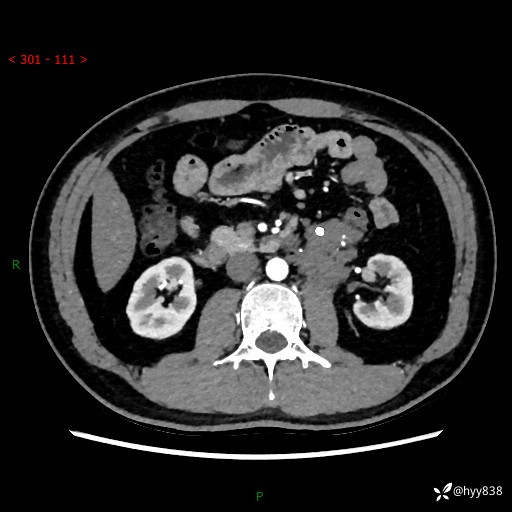

现病史:患者3月余前检查发现左侧腹膜后占位,大小约3.7*4.9cm,平素无腰疼,无肉眼血尿,无尿频尿急等不适,当时未特殊处理,在门诊复查CT提示左侧腹膜后占位,门诊拟“左侧腹膜后占位”收入院。 起病以来,患者精神佳,饮食、睡眠良好,大小便正常,体力体重无明显变化。

腹膜后CT平扫+增强